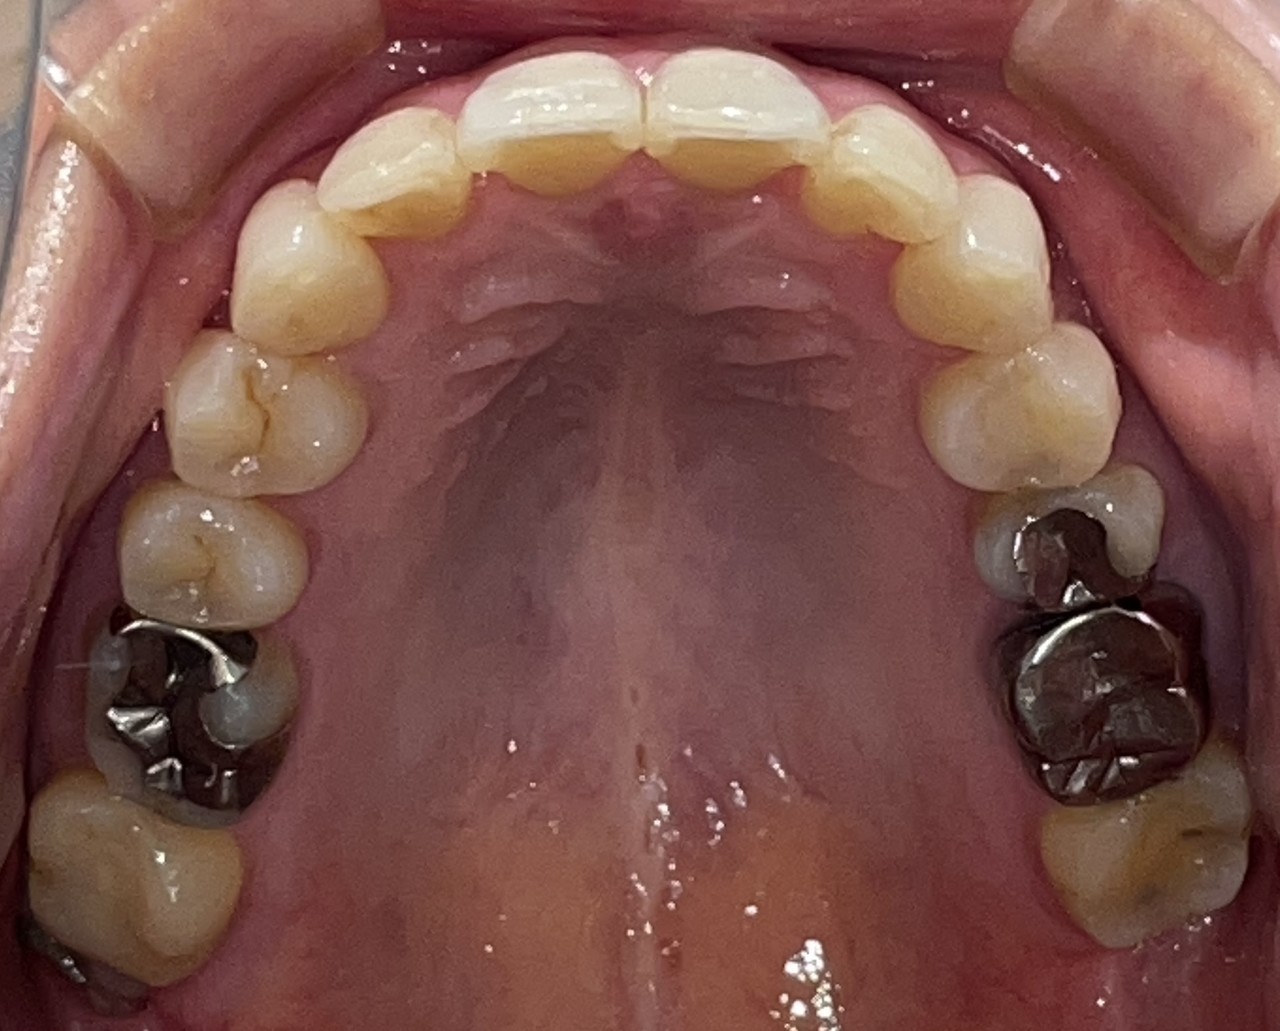

Before

After

矯正の種類 / invisalign GO

年齢・性別 / 30代男性

主訴  /  下の歯の叢生、オーバージェット、交叉咬合

治療期間 / 12ヶ月

費用 / 簡易検査 5,000円(税別) 精密検査 30,000円(税別)

両額マウスピース 450,000円(税別) 両額リテイナー料 40,000円(税別)

※マウスピース交換時別途調節料5,000円(税別)

副作用 / 口内炎・歯の移動に伴う痛み・知覚過敏 ※数日で収まる場合が多いです

リスク / 後戻り防止の為、夜のみマウスピースで保定を指示